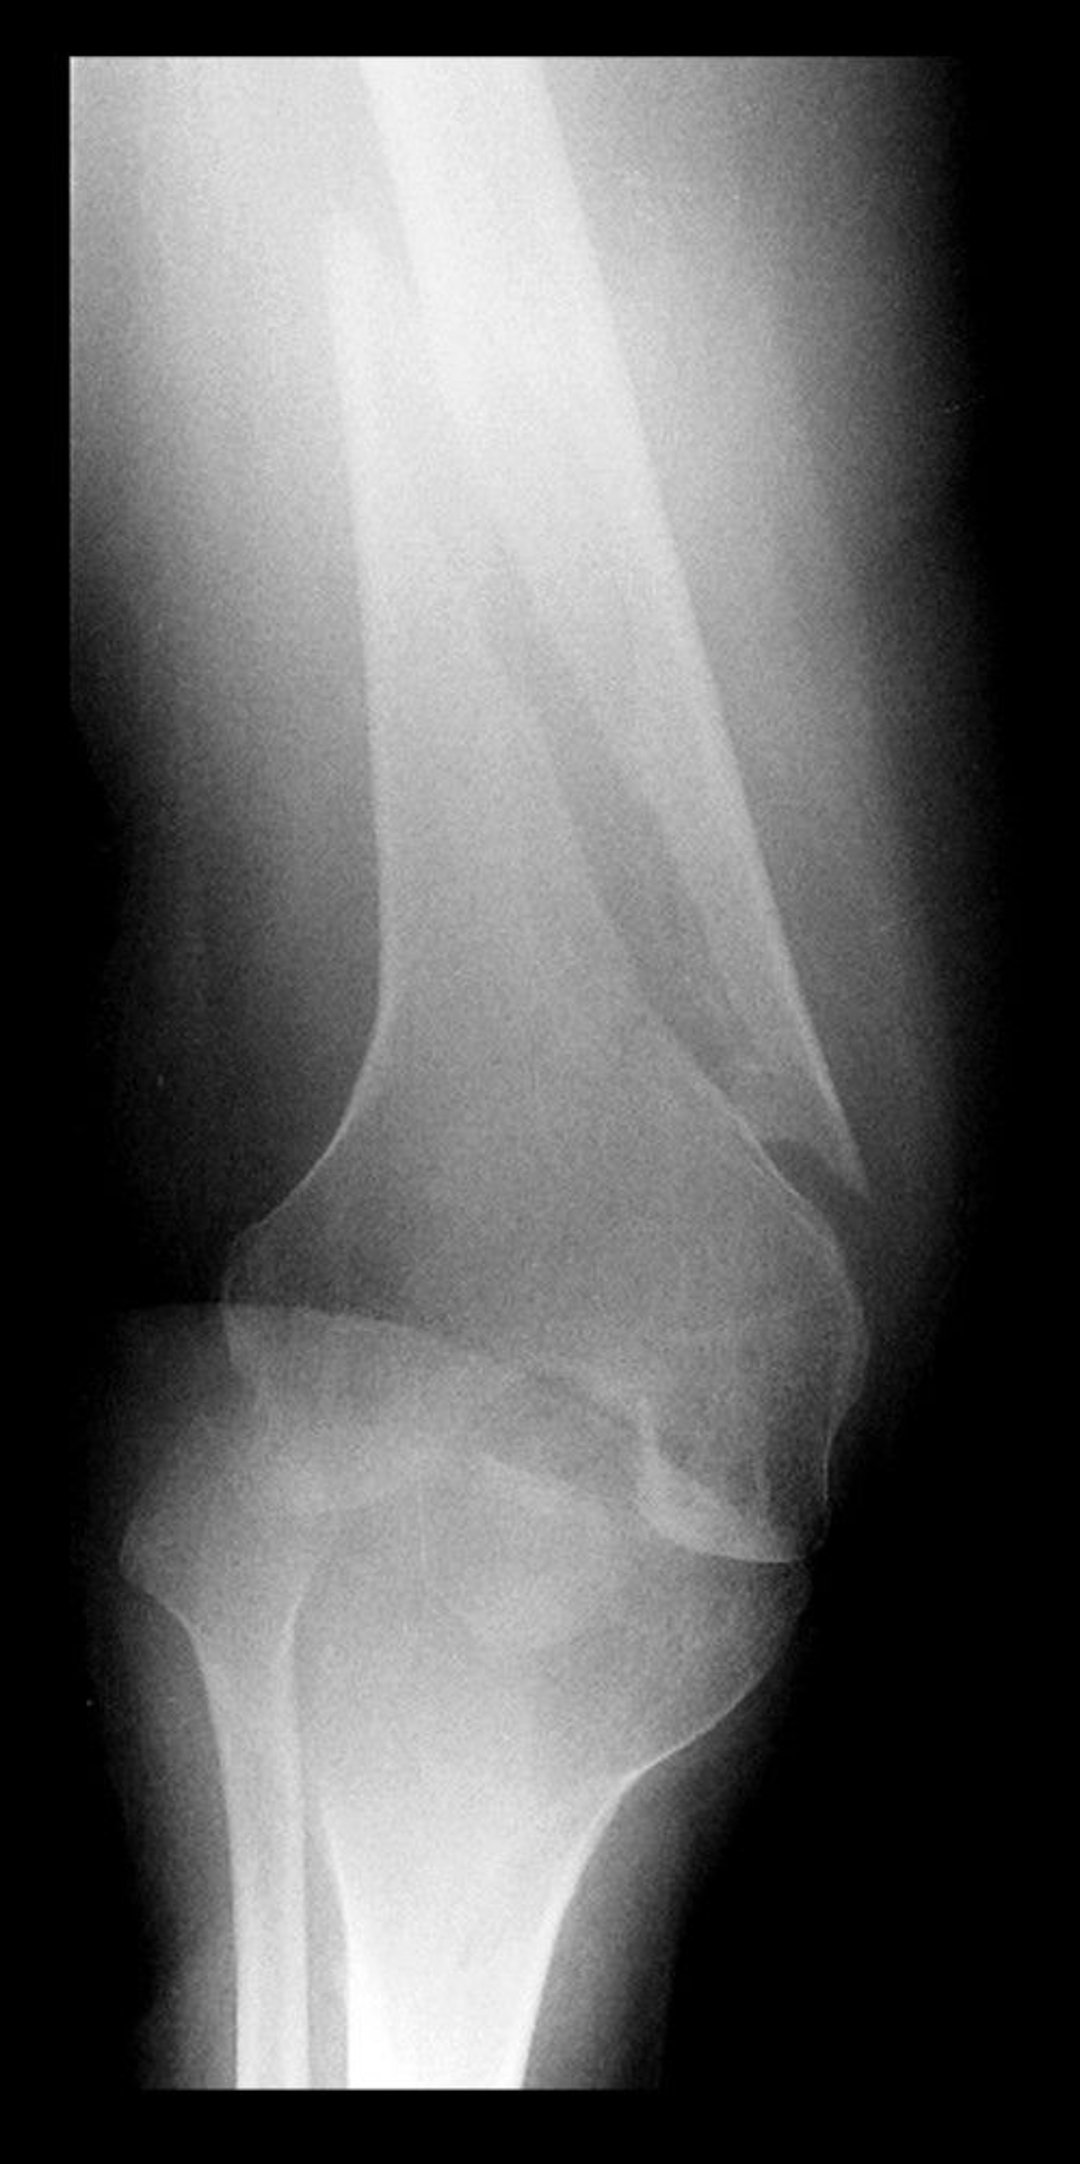

Spiral Fracture of the Distal Femur

This radiograph of the distal femur shows a lucency with a component parallel to the long axis of the bone, indicating a spiral fracture.